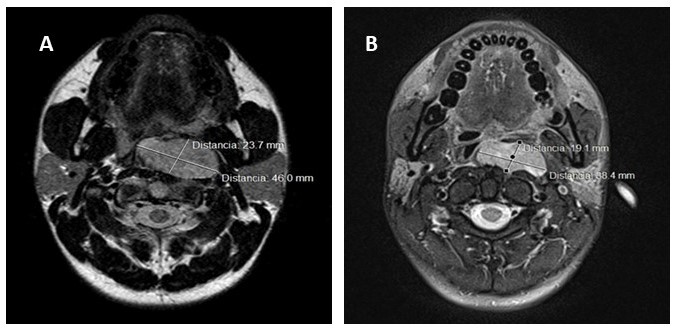

Dentro de los estudios de imagen presenta tomografía de cuello con contraste endovenoso en la cual se aprecia imagen hipodensa difusa que compromete la pared lateral izquierda de orofaringe con un diámetro de 4,28 cm x 2,83 cm, que disminuye la luz de la orofaringe y con realce heterogéneo luego de la administración del contraste, sin ganglios patológicas (Figura 3). En RMN de cuello se evidencia lesión sólida, en pared posterior de orofaringe con obliteración de la luz, de 4,3 cm x 3,71 cm, infiltrando fascia prevertebral y músculos prevertebrales adyacente a cuerpo vertebral de C2 (Figura 4). Estudios de extensión pulmonar y hepático sin lesiones sugestivas de metástasis.

En tomografía de cuello con contraste endovenoso posterior a quimio/radioterapia, se aprecia tumor aspecto heterogéneo y densidad sólida en orofaringe, sin evidencia de infiltración del espacio prevertebral ni de estructuras óseas adyacentes, sin adenomegalias. En RMN con contraste de cuello se visualiza lesión que capta contraste localizado en la pared faríngea posterior que mide 3,8 cm x 1,9 cm, impresiona tener planos de clivaje con estructuras adyacentes, sin infiltración de espacio prevertebral, que al comparar con estudio previo, se determina reducción de tamaño de lesión (Figura 5).